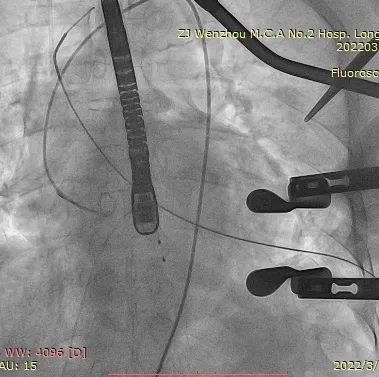

术中影像监护与评估(DSA&TEE)

瓣膜释放泥鳅导丝和单弯管过弓

加硬导丝建立轨道

介入器过瓣环平面

释放定位件

瓣膜入座

瓣膜自膨

松开锁丝,撤出输送器

DSA和TEE显示无瓣周漏,瓣膜位置、形态良好